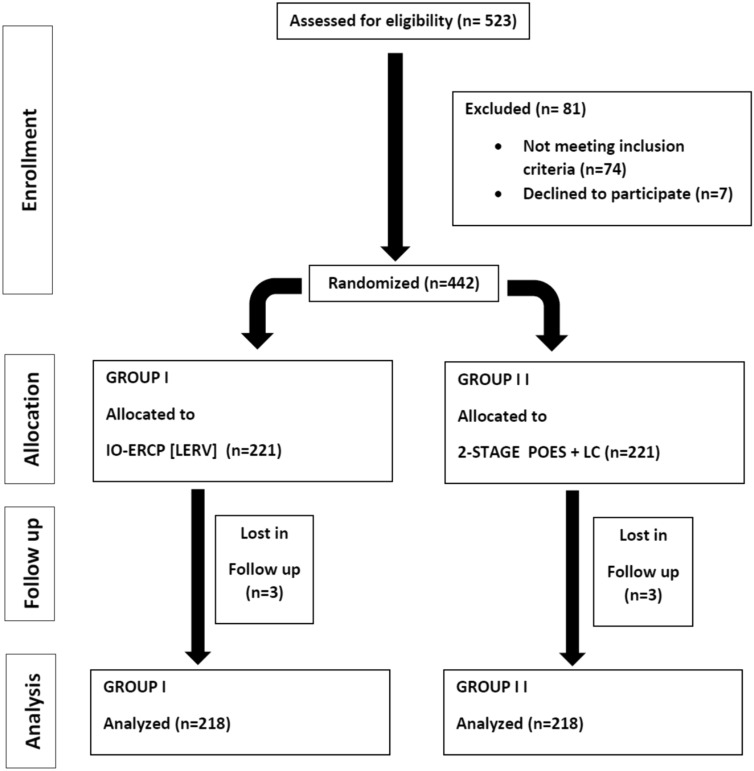

From January 2010 till April 2022 a total number of 523 patients with both gall bladder stones and with suspected or confirmed CBDS were enrolled in this study. Eighty-one patients were excluded either due to refusal to be included, incomplete data or did not complete both steps within our centers. So, a final 442 patients were randomly allocated and divided into 2 equal groups, the first group (n = 221) was treated by a single-step procedure combining LC and IOES while the second (control) group (n = 221) was treated by two-stage (sequential treatment) POES followed by LC. Scheduling for laparoscopic cholecystectomy in the control group ranged from within 8 weeks after preoperative ERCP. Six patients were lost in follow-up, so the final number of patients analyzed in this study was four hundred thirty-six patients (n = 218 for each group). The patients were randomized into two equal groups, utilizing computer-generated random numbers in sealed envelopes numbered serially. See the flow chart for the allocation process throughout the trial (Fig. 1).